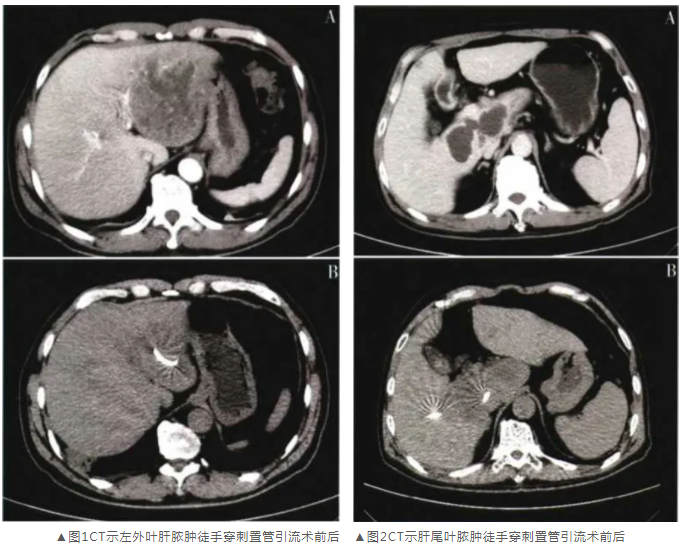

68例患者共置入71条引流管(其中3例为多发脓肿置双管引流),其中48例应用一步法,20例应用二步法。所有患者均一次穿刺置管操作成功,各抽吸出脓液25-600mL,手术平均时间约15min。几乎所有病例术后复査影像学(CT、超声)提示脓肿显著缩小、引流管位置满意(图1、2);管道 通畅性均维护良好。本组未出现明显出血、胆痿、 血气胸、胃肠道误伤等严重并发症,1个初期病例因脓液少量外溢继发局部腹膜炎经积极抗感染治疗后治愈;1例高龄患者因多发肝脓肿继发多脏器功能衰竭综合征死亡。所得脓液均行细菌培养及药敏试验,其中28例培养得肺炎克雷伯杆菌,19例培养得大肠杆菌,11例为葡萄球菌,7例为其他较少见细菌,其余未培养出致病菌;其中15例为混合致病菌感染。

▼A:术前;B:术后